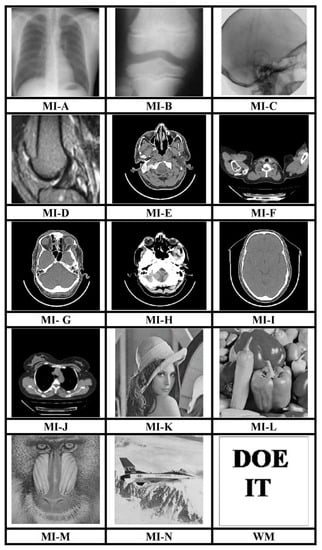

The MATLAB R2017a platform has been utilized for carrying out the experimental investigations for different gray-scale natural and MI. Both types of images that have been used for testing have dimensions 512 × 512. We have conducted experiments using a 64-bit Windows 10 Operating system with an i5 processor, 8 GB RAM, and 2.40 GHz clock speed. The different images, as well as a logo as WM, have been represented in Figure 3. The binary WM employed for authentication purposes has a 128 × 128 size. The technique is evaluated for a payload of 196,608 bits or 0.75 bits per pixel (bpp). The scheme reports an average encryption speed close to 1Mbps. The image quality metrics applied for evaluation of the scheme include normalized cross-correlation (NCC), peak signal to noise Ratio (PSNR), and structural similarity measure index (SSIM) [16,17,18,19,20]. In-depth analysis has been performed, which includes imperceptibility analysis, computational complexity analysis, and fragility analysis. Furthermore, a detailed comparison of many contemporary techniques has been described. Furthermore, the fragility analysis carried out reveals that the WM is fragile to all possible attacks and can easily detect tampering of data.

Figure 3.

512 × 512 test images and 128 × 128 binary WM.